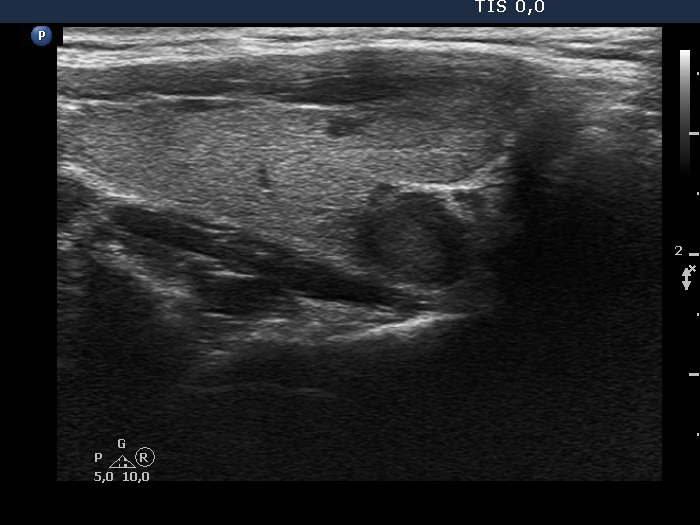

The shape of the nodule - case 2025 (ultrasonographic picture 2)

Right lobe longitudinal scan. The borders of the lesion are blurred.